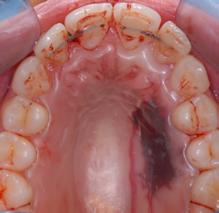

Figure 6.2.a : Parodontite chez un patient de 45 ans. De nombreux dépôts de tartre et de plaque dentaire sont visibles à la surface des dents. La gencive présente une certaine inflammation.

Figure 6.3.a : Parodontite chez un patient de 25 ans. La gencive n’est pas rétractée et seule une certaine inflammation des tissus est visible, alors que le cas est sévère.

Figure 6.3.b : Les lésions osseuses sont importantes et 80% du support osseux est détruit sur certaines dents.

Figure 6.3.a

Figure 6.3.b